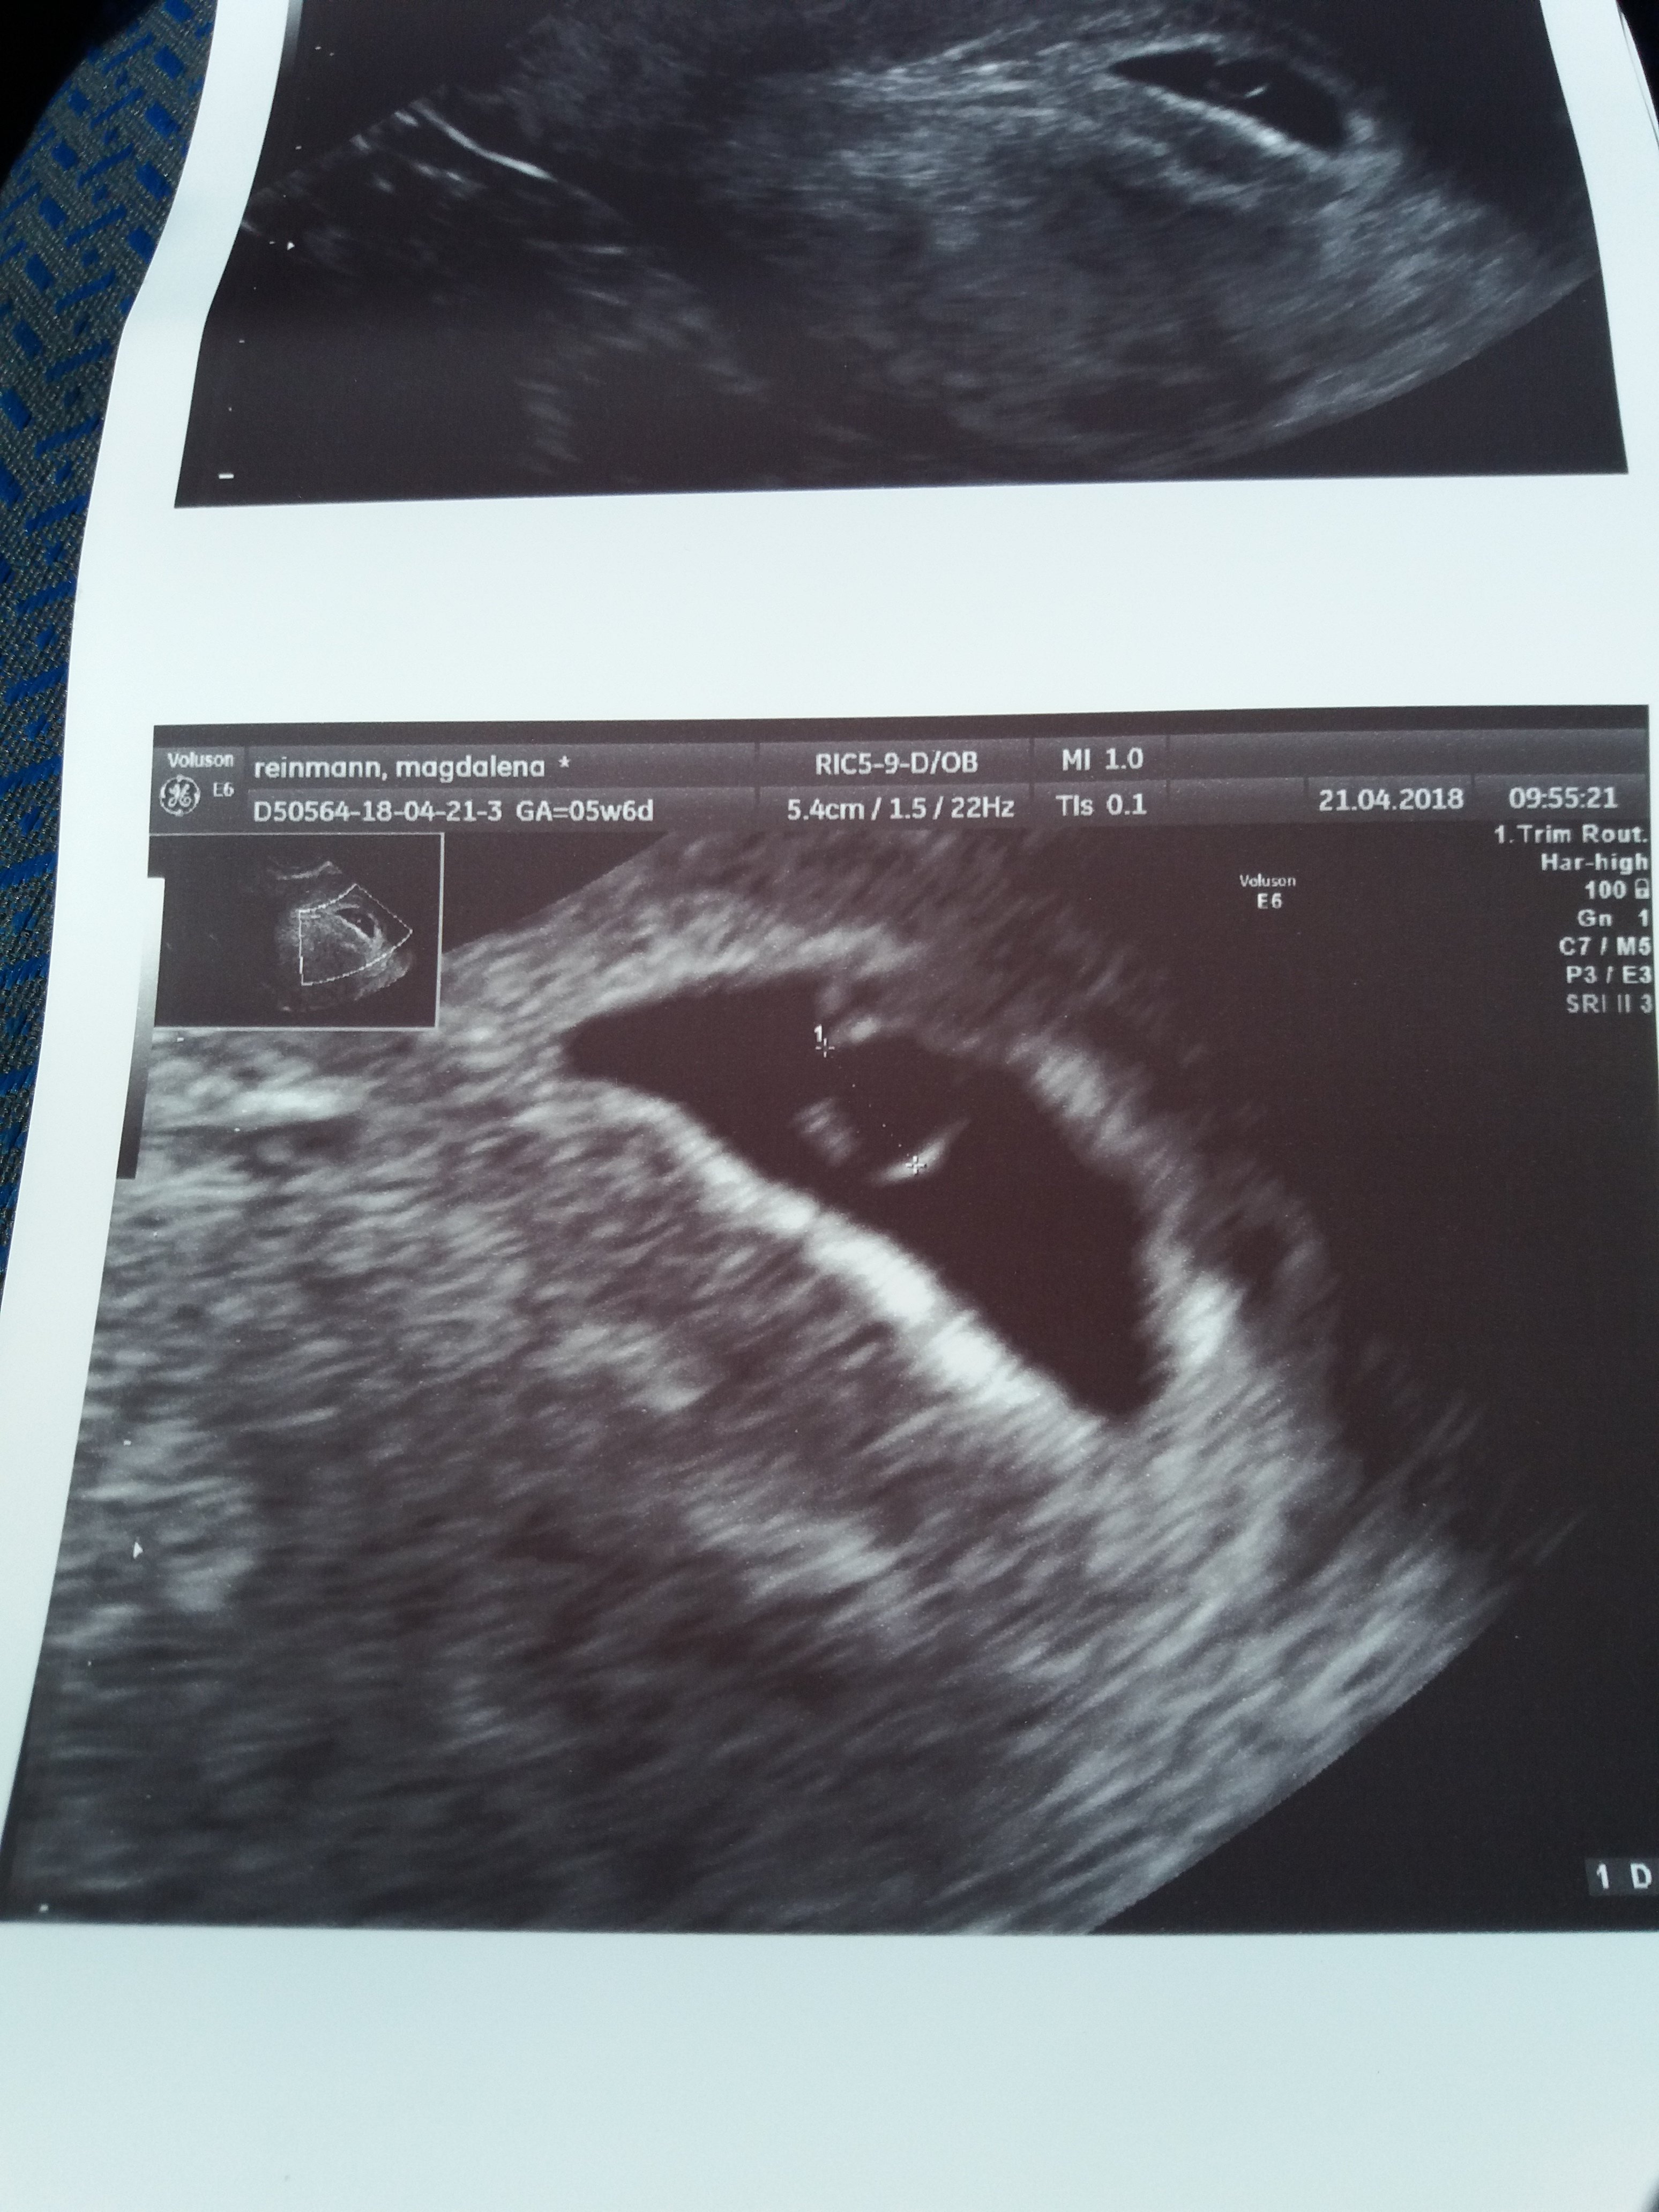

Dziewczyny, co do tego mojego Dzidziusia, to ja sobie ubzdurałam, że to prawie 3 cm, potem mąż do mnie mówi, że mam spojrzeć jeszcze raz;p

Teraz się martwię tym skąd termin z usg 4 dni różnicy, jak zarodek mógłby odpowiadać terminie OM.

No i zaczęłam się martwić, że może pęcherzyk ciążowy jest za mały, a nawet nie wiem ile ma, bo na wydruku z usg nie ma GS... a nie pamiętam, czy lekarz mówił, a ja nawet nie pytałam o GS, a chyba powinnam.

Dla mnie była istotna wielkość dziecka, że urosło i bicie serca i YS ...

@Paulinax dziewczyny już zdążyły mnie uprzedzić ;) wielkość 21mm jest jak najbardziej w porządku ;) a to że różnica jest 4 dni to nie ma się co przejmować, bo wystarczy że lekarz milimetr dalej postawi znacznik i zarodek będzie "dużo młodszy" niż les faktycznie. Także bez stresu poproszę :) bo mały ludzik wszystko czuje

ale tak na oko GS Wam się wydaję ok?:p

Dziewczyny, Waszym okiem, ten moj pecherzyk jest ok? Bo za duzo czasu mam chyba i naczytalam sie glupot w necie i martwie sie...